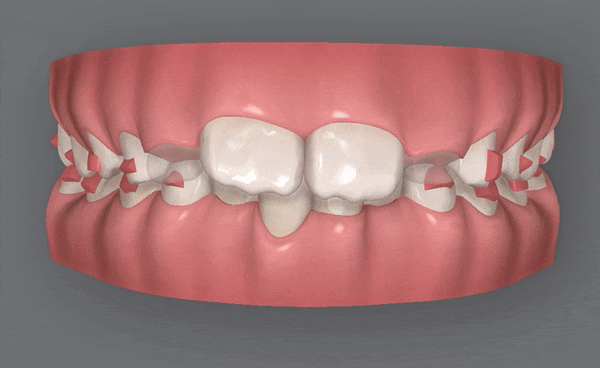

1st Clincheck (27개)

23/8~24/1

인비절라인은 ' 클린체크' 프로그램을 통해

어린이의 교합 및 정렬의 치아 관계를 평가하고, 어떻게 발전할지 예측할 수 있습니다.

첫번째 클린체크에서는 27개의 장치로 마무리 해드렸습니다.

치아가 너무 깊게 물리는 과개교합이

눈에 띄게 개선된 모습을 확인해 보실 수 있습니다 :)